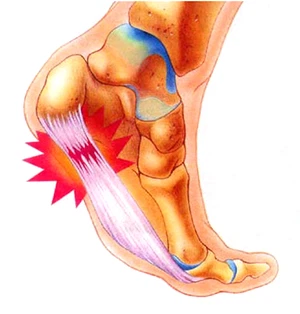

족저근막염은 쉽게 말해 발바닥 근육을 덮고 있는 막에 생긴 염증을 의미합니다. 족저근막은 발뒤꿈치뼈부터 발끝까지 이어지는 두껍고 강한 섬유로 발의 아치를 지탱해 발밑에 전달해지는 충격을 흡수하고 보행 시 발의 기둥이 되는 부분입니다.

이런 족저근막에 반복적인 미세 손상이 발생하게 되면 근막을 조직하는 콜라겐의 변성이 발생하며 이로 말미암아 염증과 진통을 보이는 질환을 족저근막염이라고 합니다.

족저 근막염 증상 중 대표적인은 것은 오전에 일어나 처음 발을 내디딜 경우 느껴지는 심각한 진통이 특징입니다. 진통은 대부분 발뒤꿈치 안쪽에서 유발생하는 경우가 많습니다. 오전에 일어나서 발생하는 진통의 경우 수면 중 경직된 족저근막이 늘어나면서 발생하는 것으로 알려져 있습니다.

족저근막에 이상이 발생하면 발뒤꿈치에 진통이 나타납니다. 진통이 내부 깊숙한 곳으로부터 나타나는데, 증상이 심할 때는 발 전체가 아파 서있기도 힘듭니다.

발끝을 발등 방향으로 구부리면 통증이 심각해지기도 하며 까치발을 들을 경우 통증이 심각해지는 것을 느낄 수 있습니다. 대부분 가만히 있을 경우 통증이 없다가 이동하기 시작하면 진통이 발생하게 되며 장시간 서있던지 걸을 경우 통증이 심각해지는 것을 볼 수 있습니다. 이런 증상과 같이 발바닥이 뻣뻣하게 경직되는 듯한 기분을 받게 되며 심각한 경우 발바닥이 타는 듯한 작열감을 느끼게 됩니다.